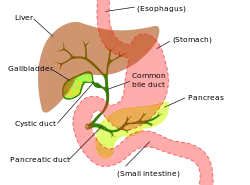

9. Gallbladder.

10–11. Right and left lobes of liver.

12. Spleen.

13. Esophagus.

14. Stomach.

15. Pancreas: 16. Accessory pancreatic duct, 17. Pancreatic duct.

18. Small intestine: 19. Duodenum, 20. Jejunum

21–22. Right and left kidneys.

The front border of the liver has been lifted up (brown arrow).[1]

The pancreatic duct, or duct of Wirsung (also, the major pancreatic duct due to the existence of an accessory pancreatic duct), is a duct joining the pancreas to the common bile duct. This supplies it with pancreatic juice from the exocrine pancreas, which aids in digestion.

The pancreatic duct joins the common bile duct just prior to the ampulla of Vater, after which both ducts perforate the medial side of the second portion of the duodenum at the major duodenal papilla. There are many anatomical variants reported, but these are quite rare.[2]